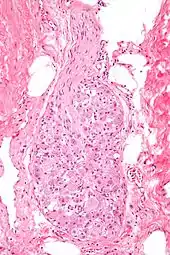

Mikrografi af et ganglion. Farvet med hæmatoxylin-eosin.